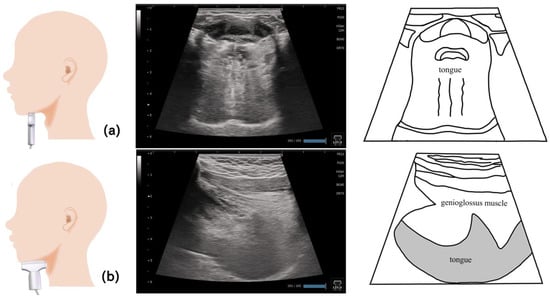

6. Tongue (Figure 4)

8. Genioglossus Muscle (Figure 7)